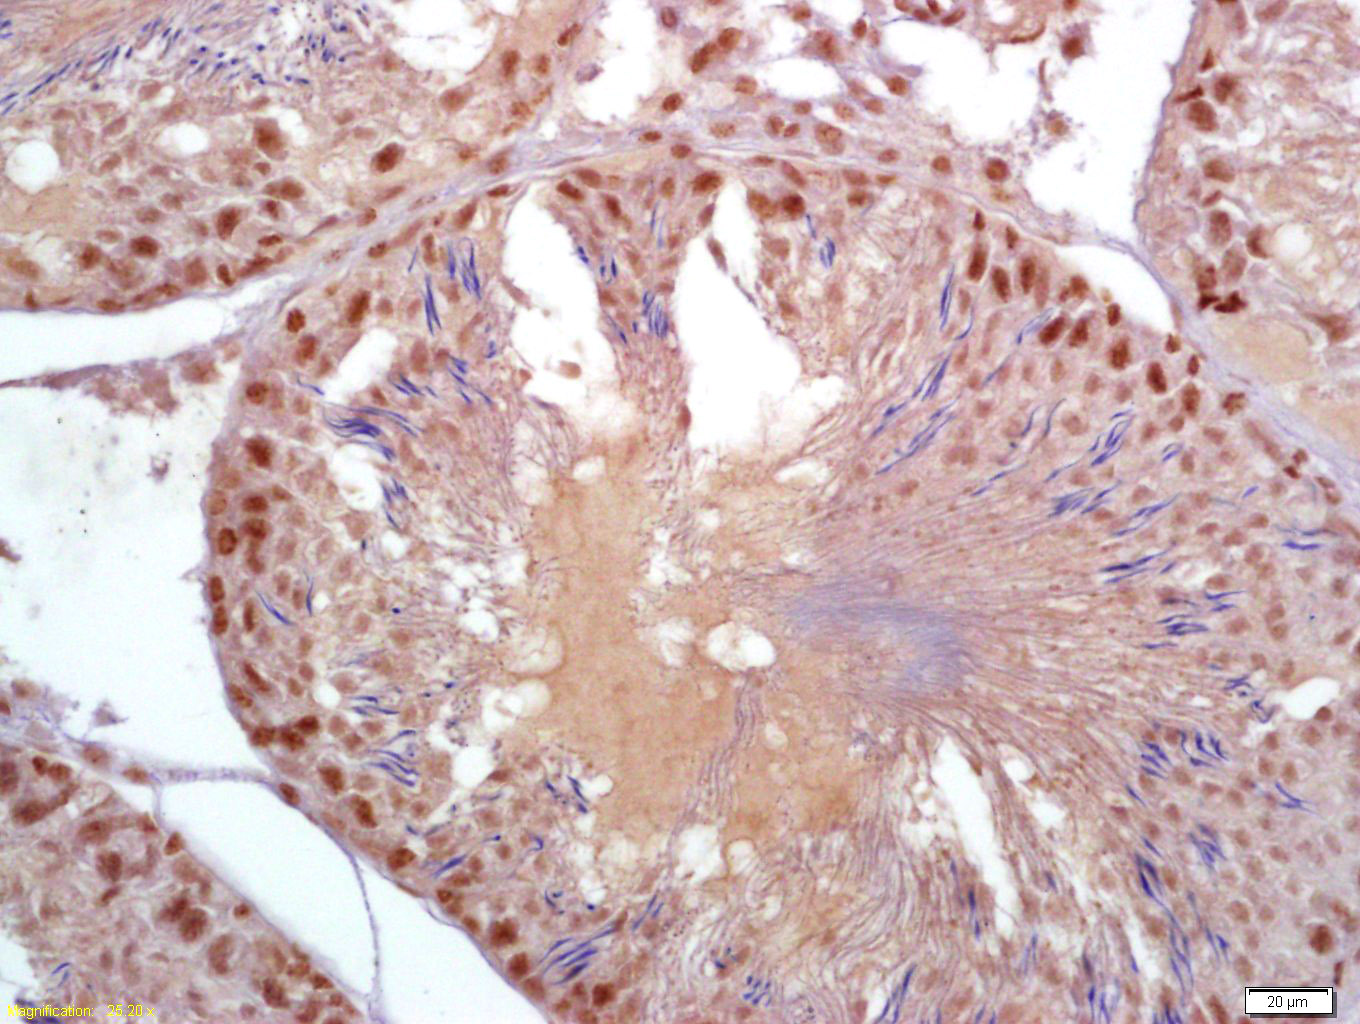

| IHC-P | Rat | Human, Mouse, Pig | 1:100-500 |